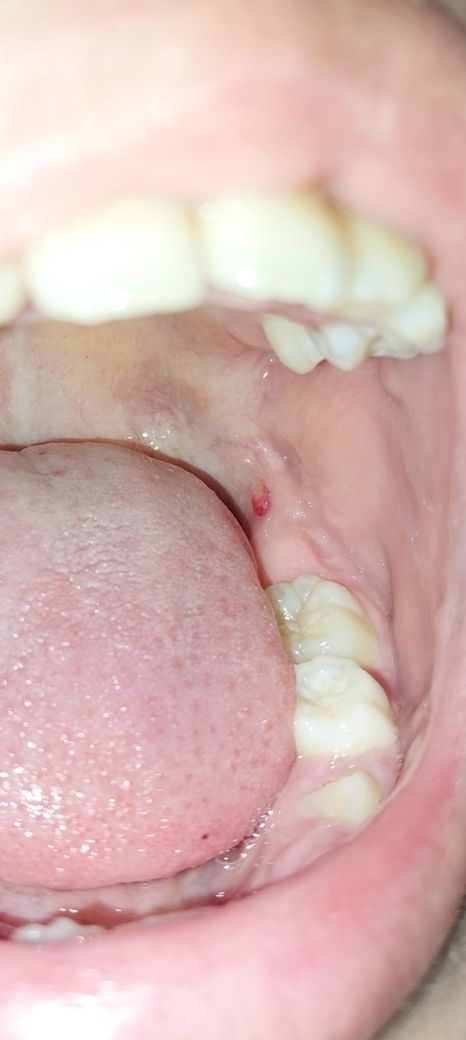

아이 입속에 이상한게 났는데 뭔지 궁금해요.

초4아이 입속에 빨갛게 뭔가가 났는데

커졌다가 줄었다가 하면서 거슬린다고 합니다

통증은 딱히 없다고 하는데 저게 뭔가요?

아이 말로는 줄곧 저자리에 뭐가 튀어나와있어서 커졌다 작아졌다 했던것 같다고 하는데

본인이 그동안 봤을때는 그냥 살색이었는데 오늘보니 빨갛게 되었다고 하네요.

• 2번 째 사진

아마도 자극에 의해 상처가 나는 것으로 보입니다. 아니면 깨물려 상처가 나면 저런식으로 물집 같이 생기기도 합니다. 그냥두면 없어질 것으로 보입니다.

단순 잇몸에 물집이 잡힌거 같습니다. 터트리면 될것같으니 너무 걱정하지 않으셔도 될것같습니다.

사진으로 봤을 때는 점액종으로 보입니다. 점액종은 점막 조직이라고 과연 자극을 받았을 때 점액 내부에 조직 액이 차면서 생기게 됩니다. 그게 문제가 되는 것은 아니며간단히 제거할 수도 있습니다. 자세한 확인을 위해서 치과에서 진료를 받아보는 것을 권해드립니다.